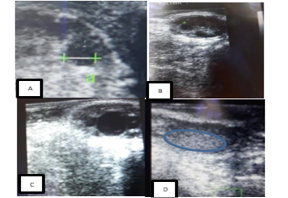

Figure 1

Ultrasound images of a cow’s ovaries in this study. (A) This image shows to get diameter of follicle or corpus luteum, (B) these images show five follicles, (C) these images show one dominant follicle, and (D) these images show of corpus luteum.